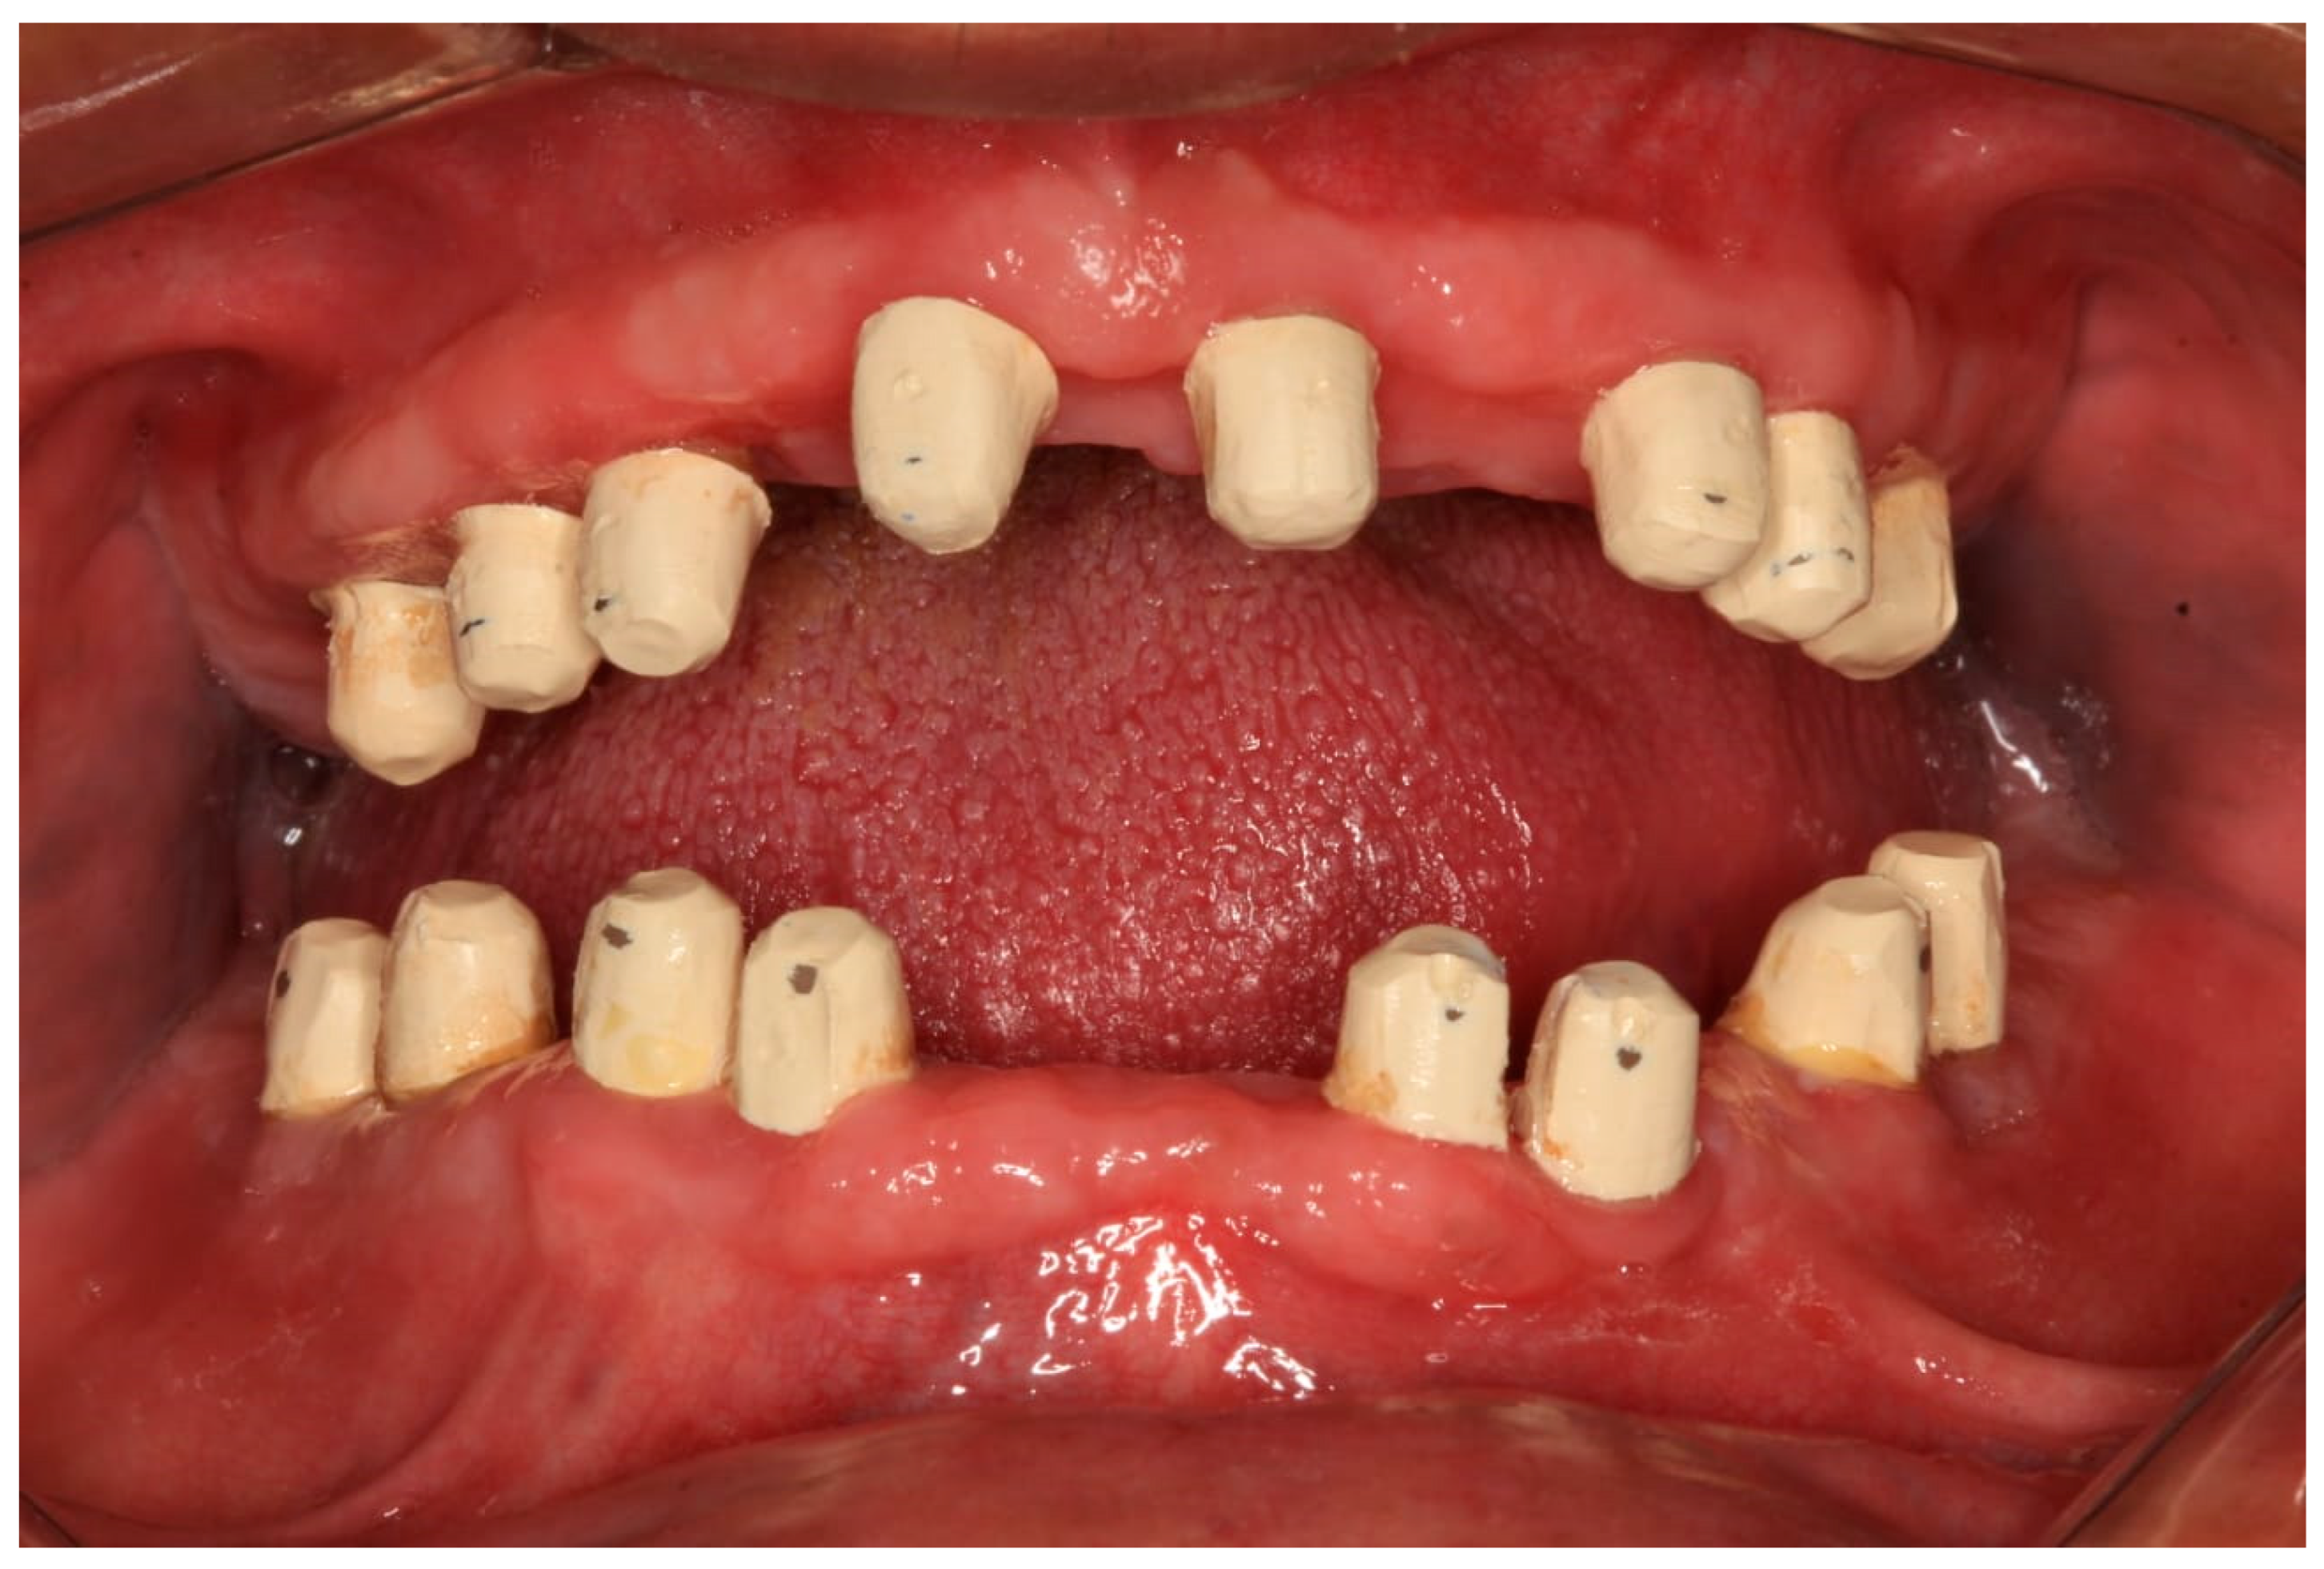

The single-piece dental implants exhibited non-parallel alignment, as confirmed on the final STL file. To manage this, a conventional, clinically approved approach was used. Polyether ether ketone (PEEK) telescopic crowns were fabricated to harmonize the prosthetic path of insertion, align the implants, and provide a cushioning effect beneath the planned rigid bridges. The STL files guided fabrication to achieve a parallel insertion path.

PEEK has been conventionally used for single crowns and for larger cross-arch removable partial dentures [27]. The novelty in this case lies in adapting PEEK as telescopic crowns to support a fixed bridge over single-piece implants, thereby aligning non-parallel fixtures and achieving a predictable path of insertion. As this report describes a single retrospective case treated within the scope of established clinical practice, institutional review board (IRB) approval was not required. However, IRB clearance was later obtained to support publication and ensure compliance with ethical reporting standards.

Each telescopic crown was sandblasted on the internal surfaces, then placed in an ultrasonic bath and treated with the manufacturer-specified “Bredent” solution. A resin cement was utilized to bond each telescopic crown to its respective zirconia abutment. The arches were scanned once again and sent to the lab for the fabrication of segmented zirconia bridges, which were subsequently provisionalized with PEEK crowns (Figure 11, Figure 12 and Figure 13).

Figure 12. PEEK telescopic crowns are shown covering the implants’ abutments.